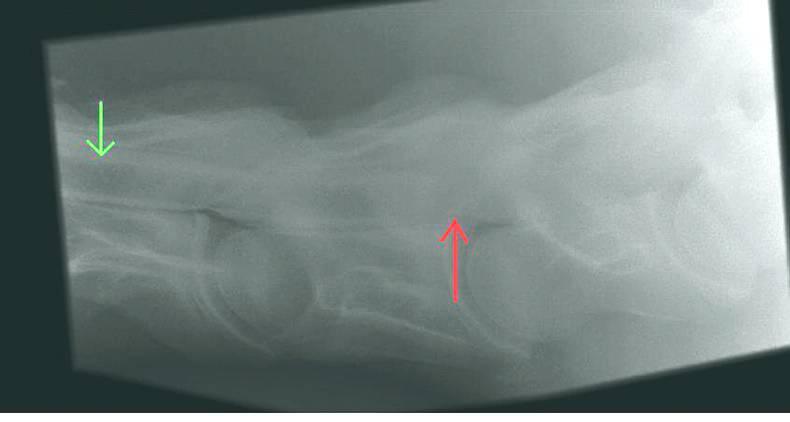

WOBBLER Syndrome or ‘Cervical Vertebral Malformation’ is a neurological condition seen in young horses which causes them to have an abnormal ‘wobbling’ gait.

In a normal horse, a message is generated in the brain and is transmitted through the spinal cord. The spinal cord travels through the spinal canal which is formed by the adjacent vertebrae of the neck and back.